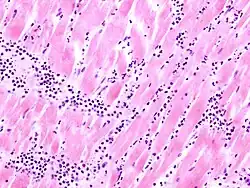

![]() |

Old myocardial infarction

Mikro: Bindegewebige Narben, Fibrozyten mit z.T. großen ovalen Zellkernen. Kompensatorische Hypertrophie der umgebenden Myozyten. Gute Darstellung in der EVG-Färbung: Herzmuskel grau, Narbe violett.

Makro: Fibrosiertes Areal mit Lipomatosis cordis.